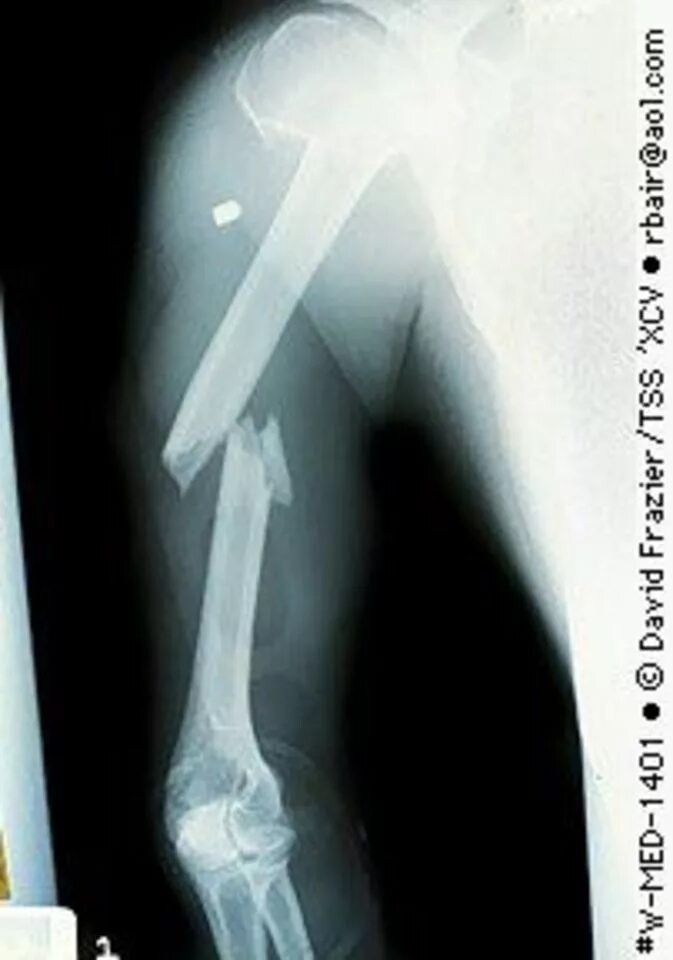

Снимок перелома со смещением